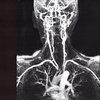

a história do fluxo sanguíneo

corpo em decadência